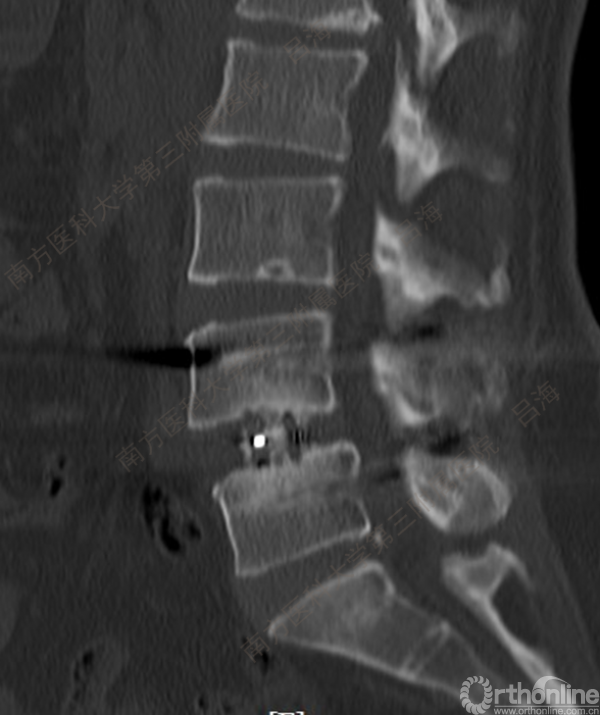

随着社会老龄化进程加快,胸腰椎退行性病变的治疗已经成为脊柱学术界的一个热点话题。MIS-TLIF手术可以治疗多种不同的胸腰椎退行性疾病,南方医科大学第三附属医院吕海教授结合病例为我们一一展示了该术式在治疗不同胸腰椎疾病时的具体手术过程。